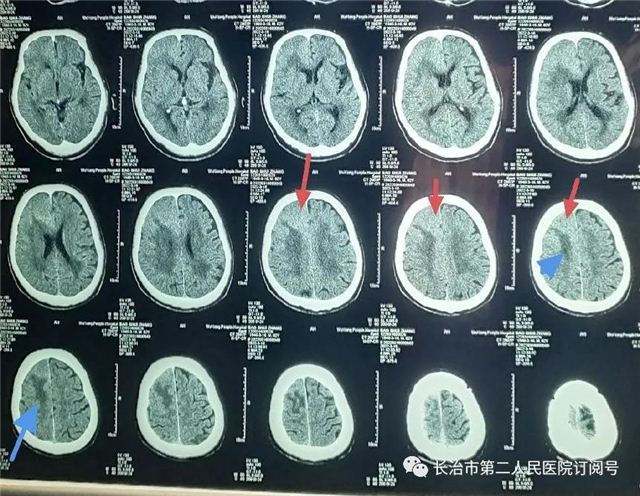

▲CT发现左额叶占位,局部脑组织水肿

术前检查见右额占位,强化明显,患者血糖27mmol/L,老慢支、肺气肿四十余年,血气分析:氧分压55.7%(参考值83-108%),氧合指数169mmHg(参考值400-500mmHg),经科室讨论,内分泌科、呼吸内科、心内科、麻醉科评估手术风险后在全麻下行开颅颅内肿瘤切除术。